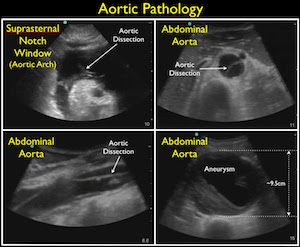

How do you evaluate the PIPES?

- Component: Aorta

- Probe: Phased array probe (3.5 – 5 MHz)

- Location: Longitudinal and transverse views of aorta at 4 levels (infracardiac, suprarenal, infrarenal, and right at the iliac bifurcation)

- Measurement >3 cm is abnormal. If >5 cm consider ruptured AAA if no other cause found.

- Most AAAs located below the renal arteries